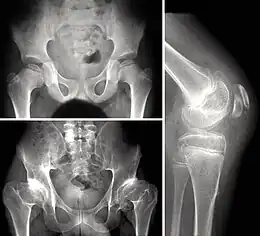

La dysplasie épiphysaire multiple ou maladie de Fairbank est une chondrodysplasie caractérisée par une atteinte des épiphyses, responsable de douleurs articulaires précoces, d'ostéochondrites répétées et d'arthrose précoce[1].